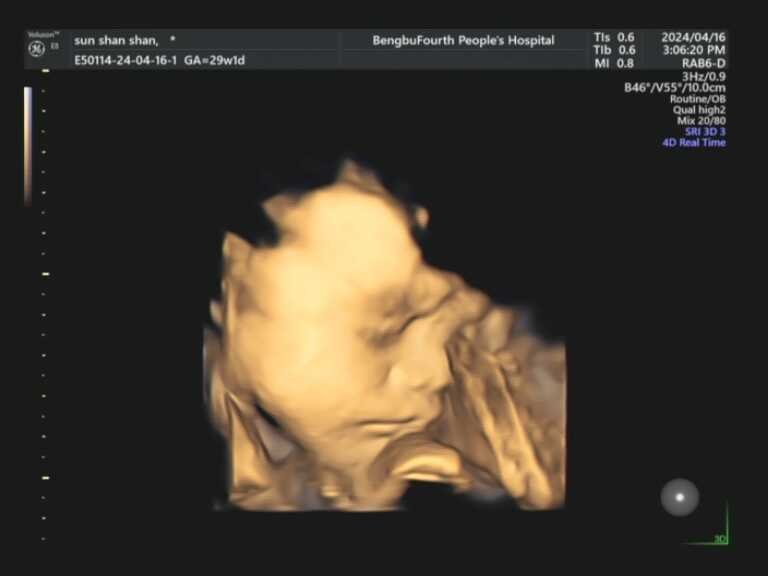

亲爱的准爸准妈,您是否无数次在梦中勾勒宝宝的模样?想象宝宝是像爸爸一样有着高挺的鼻梁,还是像妈妈一样爱笑?现在,您无需再等待十月之久。蚌埠市第四人民医院(市康复医院)高新院区超声科引进超高端美国GE-E8四维彩色超声诊断仪,将为您开启一场奇妙的生命探索之旅。这款被誉为“超声界网红”的设备,是胎儿排畸的顶端配置,搭载全球先进的电子曲面矩阵4D探头,能360°立体清晰展示胎儿各器官发育情况,精准捕捉每一个细节。

在这里,您将看到宝宝在子宫里打哈欠、吮手指、微笑、伸懒腰的可爱瞬间。在这里,您将获得宝宝人生中第一段动态“写真”和“照片”,成为您家庭最珍贵的回忆。

孕22-24周,是做四维彩超的最佳时间段。因为这段时间胎儿的各项器官已经基本发育完全,且羊水较多,更加容易观察胎儿的生长发育状况,孕妈妈们一定要提前预约。